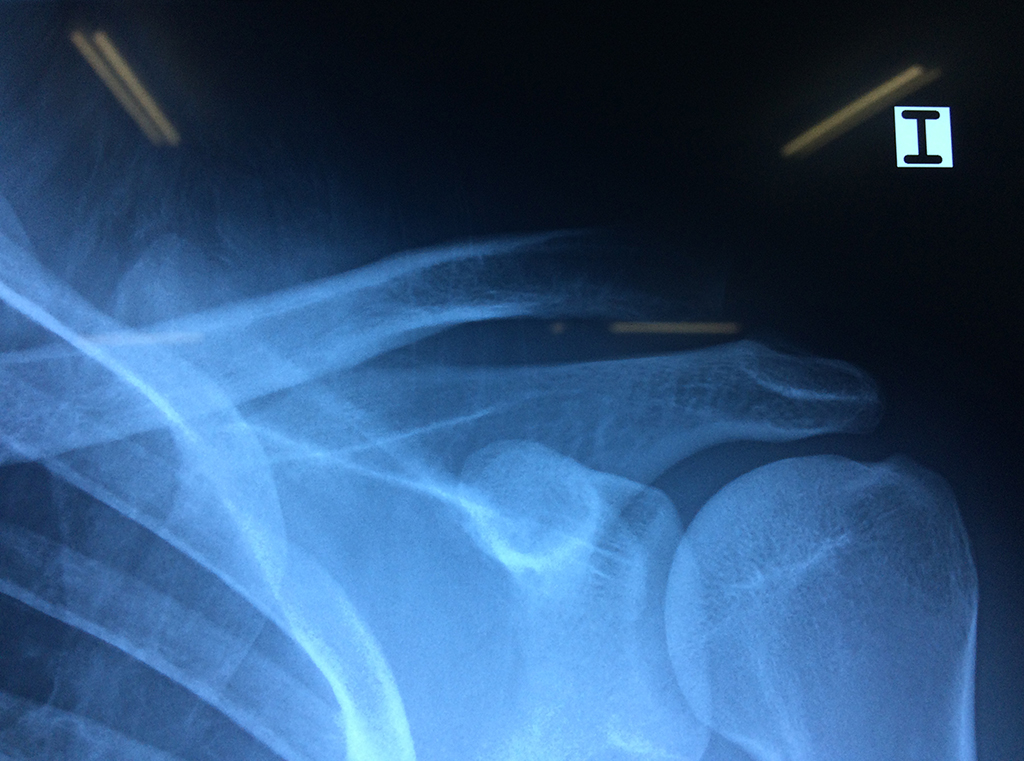

Exteriormente una envoltura de tejido blando circunda el conjunto, es la llamada cápsula articular que está reforzada por varios ligamentos que le dan estabilidad e impiden que los huesos se desplacen más allá de sus límites fisiológicos. Un conjunto de músculos y sus tendones se unen a las superficies de los huesos y hacen posible la movilidad de la articulación, entre ellos es muy importante el manguito rotador formado por cuatro músculos que proporcionan movilidad y estabilidad al hombro.